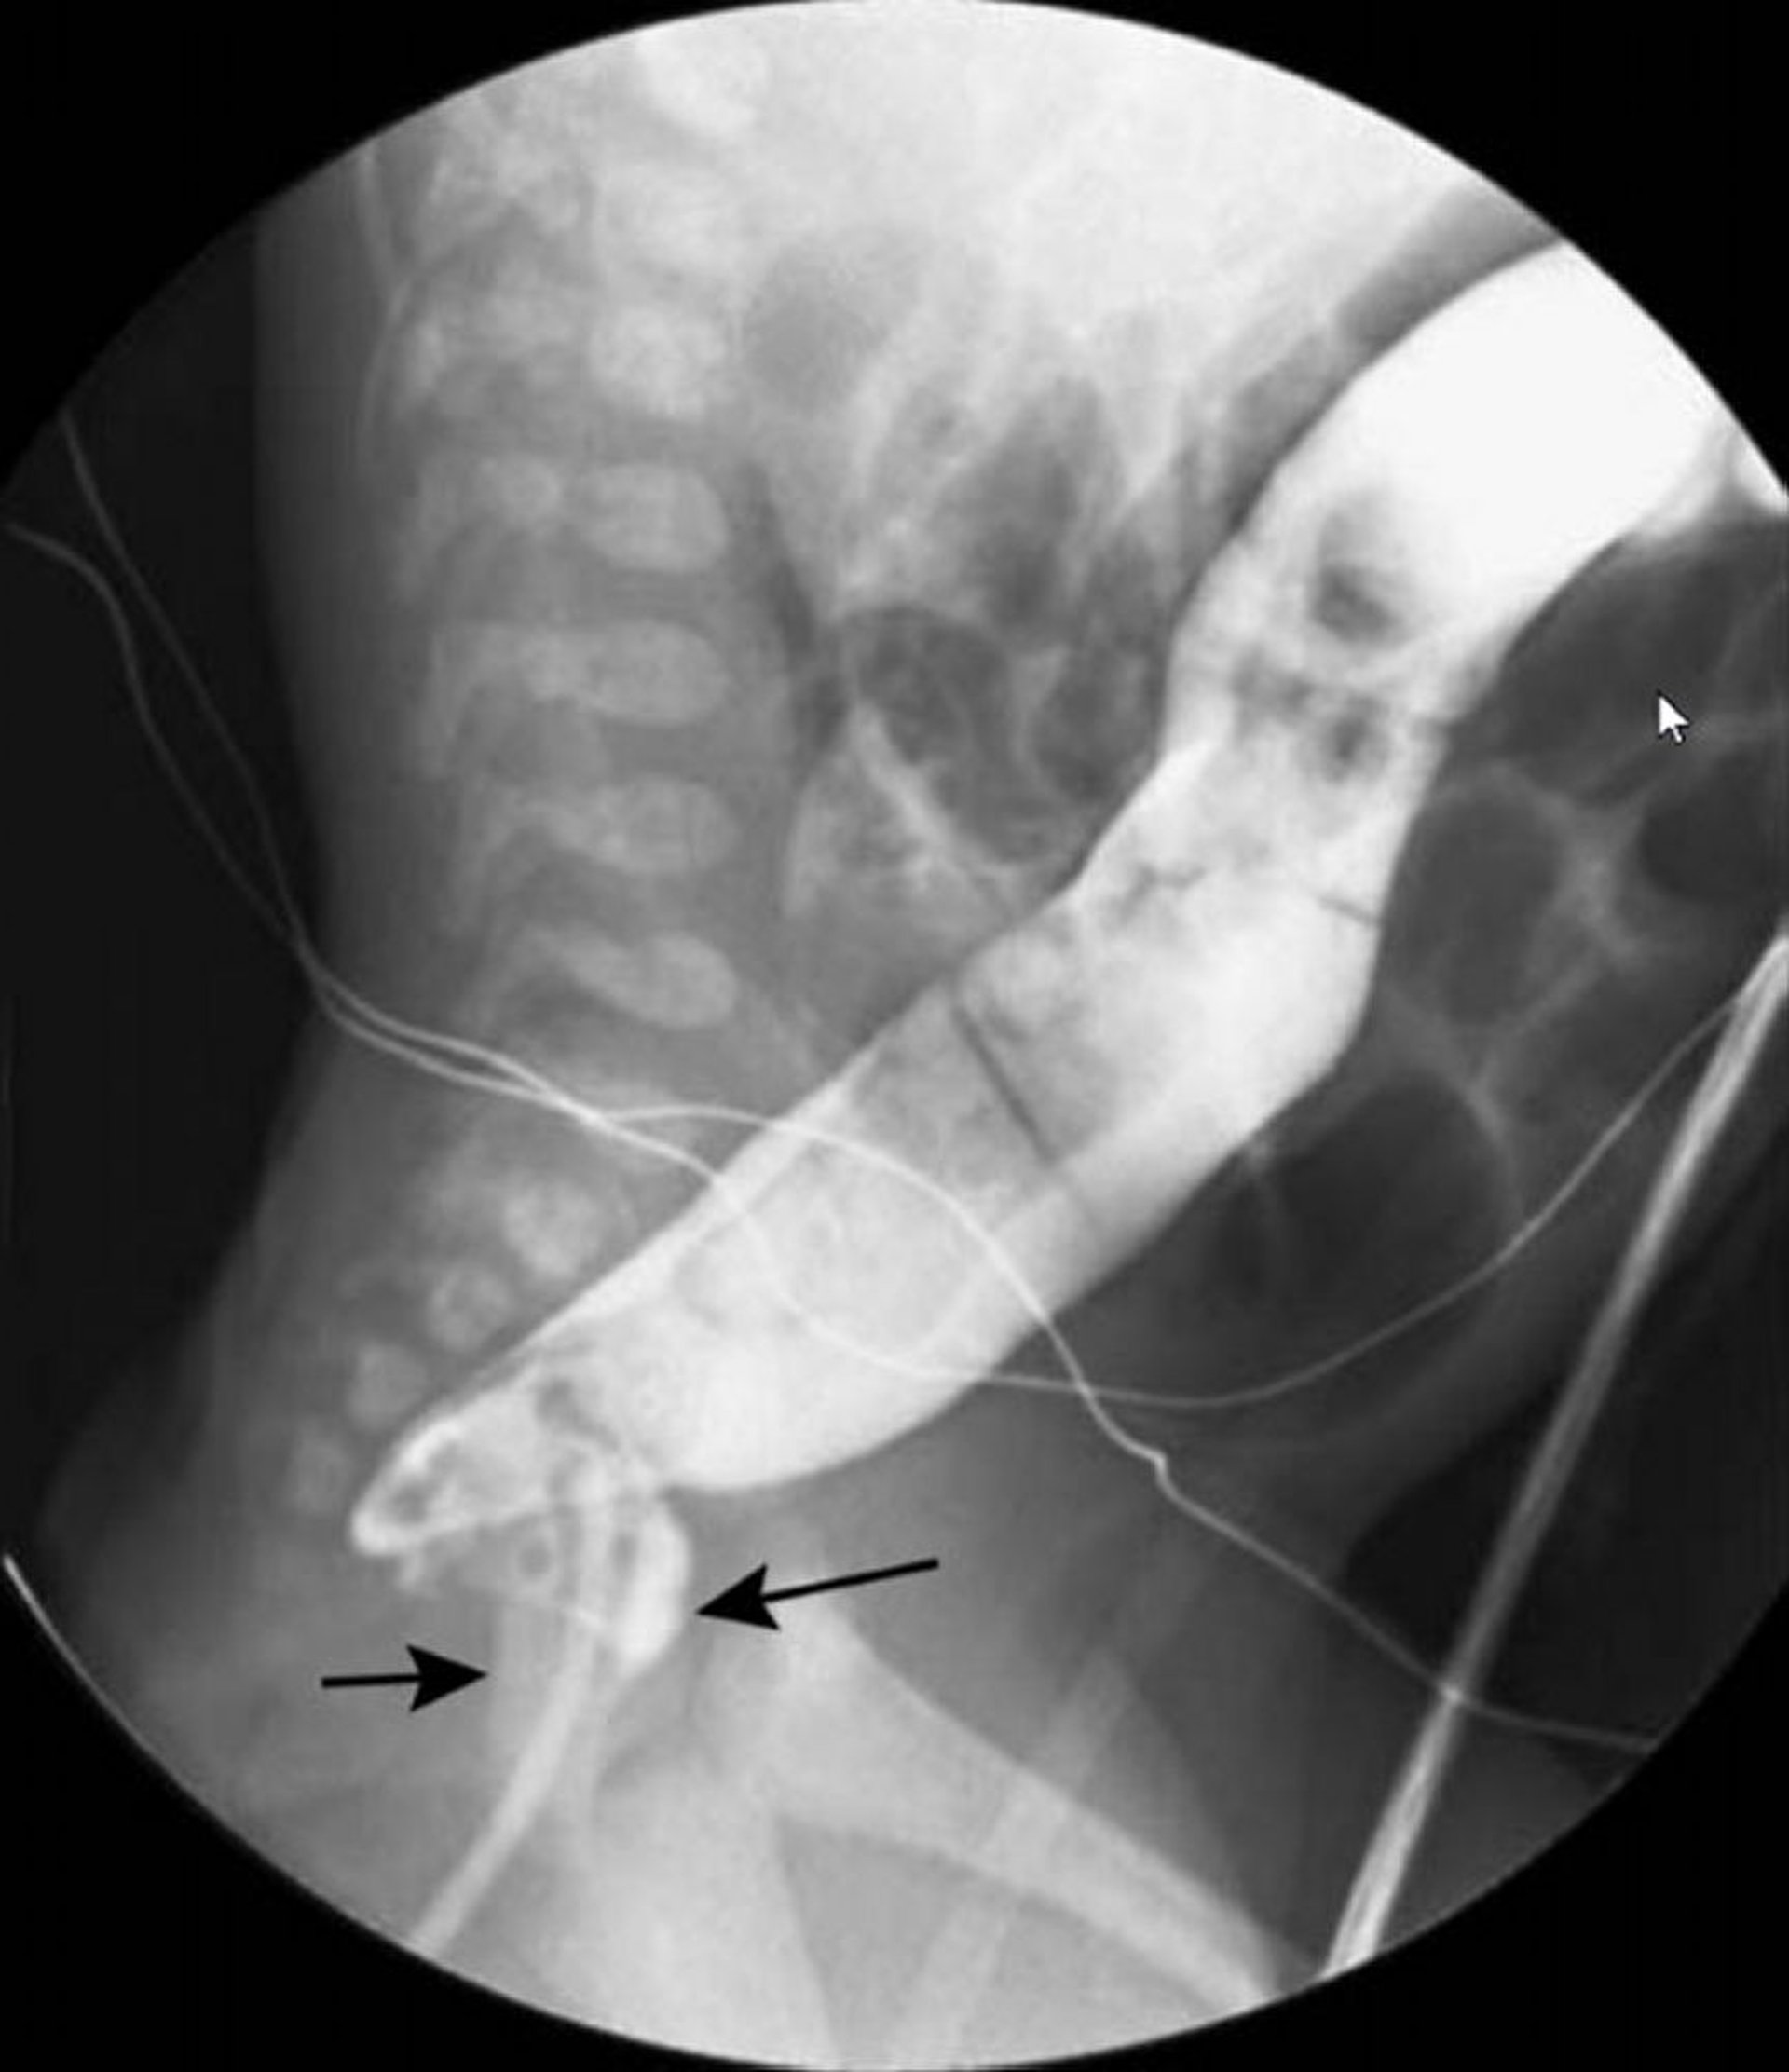

Одноконтрастная бариевая клизма, показывающая деформации в виде "шеи лебедя" при болезни Гиршпрунга

На этом изображении бариевая клизма показывает суженную прямую кишку (черные стрелки) и расширенную толстую кишку (белая стрелка) проксимальнее.